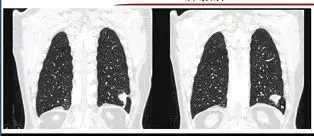

4. 肺内淋巴结

肺内淋巴结在体检中也较为常见,肺内淋巴结的影像特点主要以下特点:贴近胸膜;位于肺小叶的不同部位,其形态多变,三角形、圆形、扁圆形、梭形、五角形等都是常见的肺内淋巴结形状。

肺内淋巴结通常需要与肺腺癌进行鉴别诊断,腺癌结节通常中心位于肺内,这一特点能够与肺内淋巴结贴近胸膜的特点进行区分。

图7 肺内淋巴结鉴别诊断